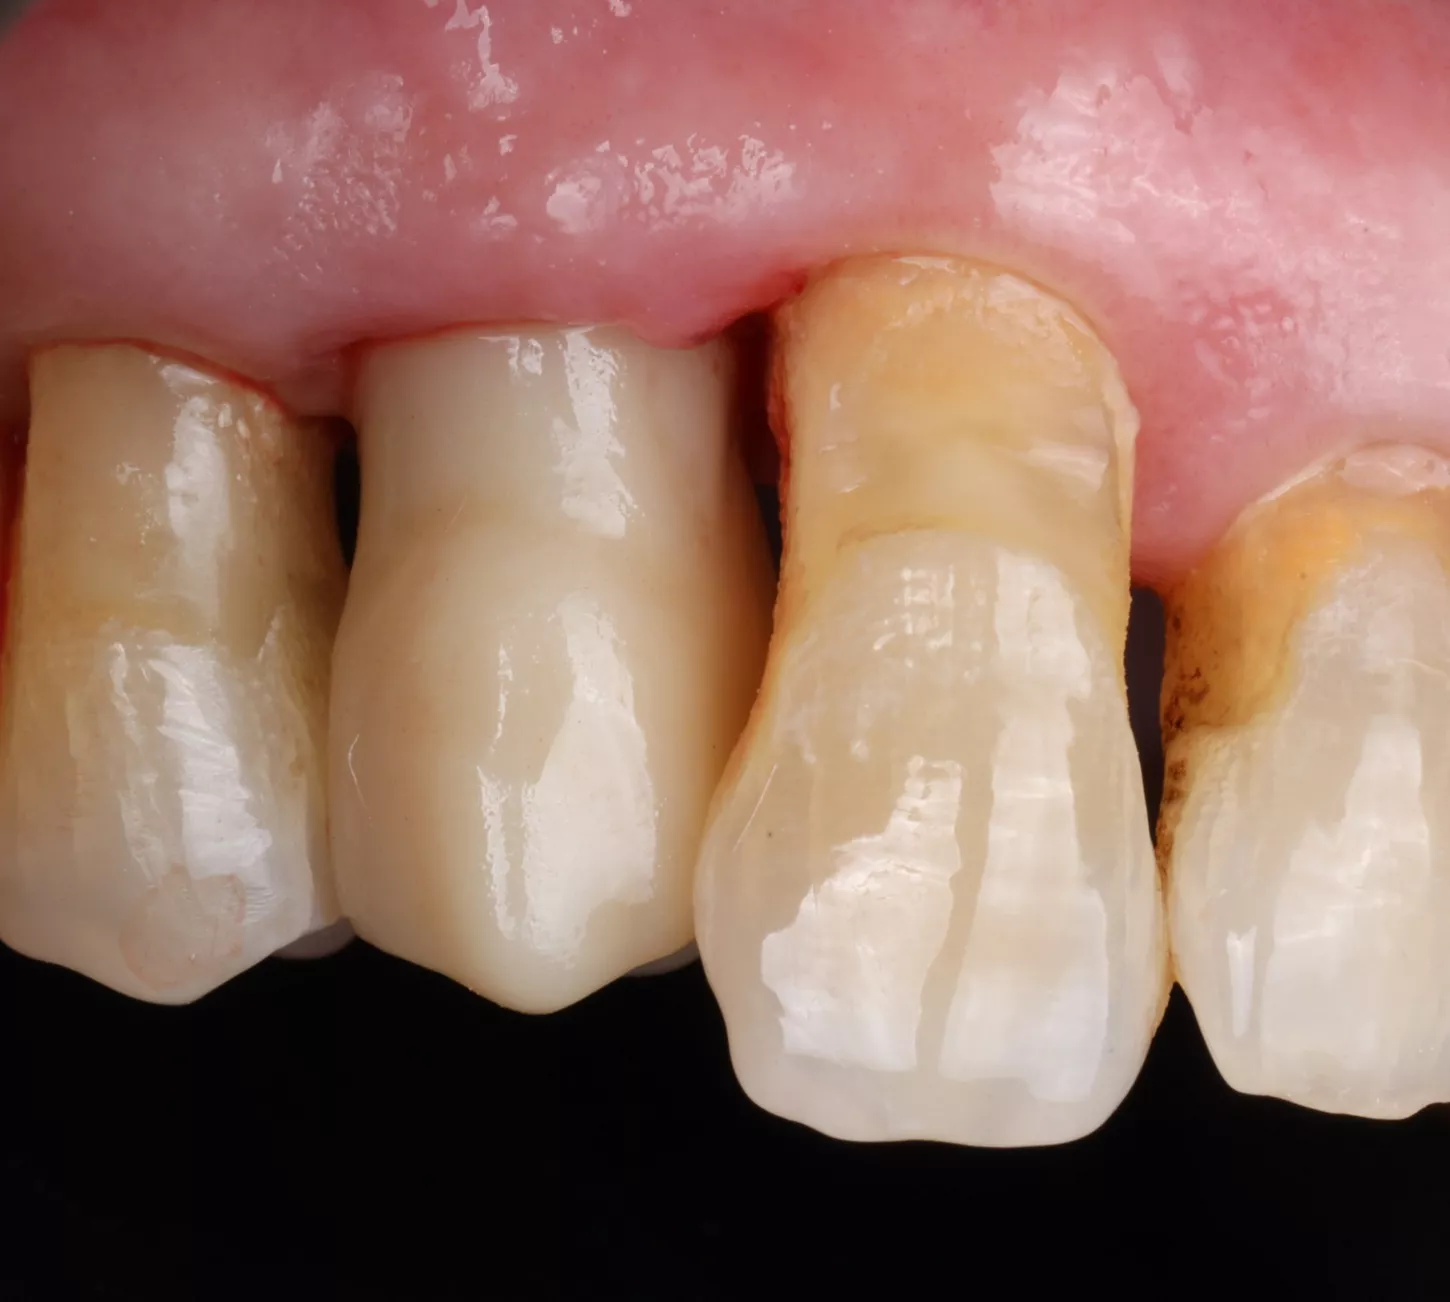

A 78-year-old male in good general health, with no medication and a negative smoking history, presented with mobility of the maxillary right second premolar (tooth 15) (Fig 1a. 1b). Clinical examination revealed severe occlusal wear, plaque accumulation, subgingival calculus, bleeding on probing, and multiple carious lesions. Periodontal assessment showed probing depths >10 mm and grade III mobility. CBCT confirmed circumferential vertical bone loss around tooth 15 and generalized periodontal involvement, indicating a hopeless prognosis and the need for extraction (Fig 1c).

1a. 1b. 1c. CBCT and panoramic views showing severe bone loss around tooth 15, confirming hopeless prognosis.